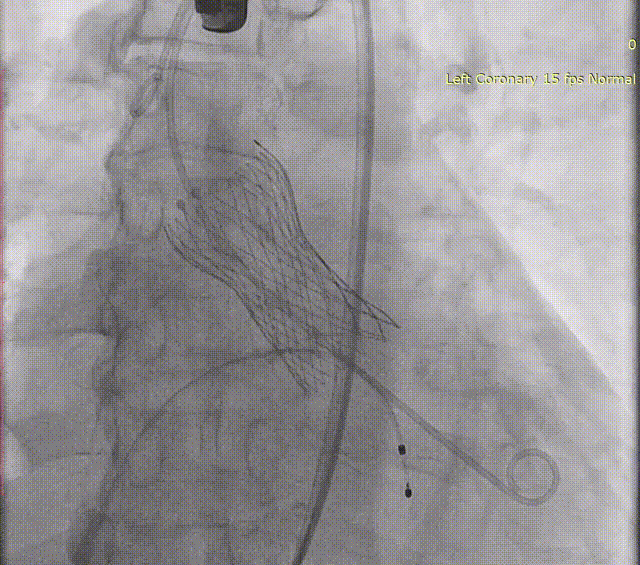

LAAC手术过程

TAVR手术完成后,在TEE指导下,白明教授顺利偏下偏后完成了房间隔穿刺,同时TEE再次检查左心耳开口19-20mm。DSA造影观察与术前CTA多平面重建结果吻合,左心耳浅鸡翅型,测量左心耳开口24.9mm深度22mm。经过充分讨论和手术策略分析,决定为患者使用WATCHMAN FLX™ 31mm封堵器进行左心耳封堵。WATCHMAN FLX™器械由于和WATCHMAN设计的不同,导引鞘不需要进入左心耳远端,即可安全展开封堵器。术中白明教授送入WATCHAMN FLX™ 31mm输送系统后,退鞘形成FLX BALL,后采用进退结合法,“毛毛虫”式展开封堵器。造影观察封堵效果理想,牵拉试验稳定,在TEE上观察封堵器微露肩,压缩比21%,各角度无残余分流,最终释放左心耳封堵器。术后观察患者心包积液相比术前无变化,生命体征平稳,一站式手术顺利完成。